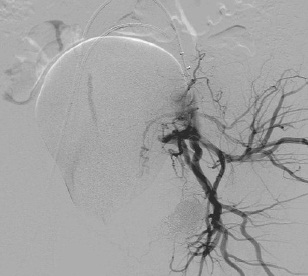

女性盆腔血管实物图

女性盆腔血管分布图

女性盆腔血管分布主要:是膀胱、生殖器官和直肠、是植物神经功能紊乱、事站立工作、子宫后位、长期便秘、早婚早育、孕产频繁的人,以及患有盆腔炎、附件炎、子宫内膜炎等炎症时,静脉血流量增多,盆腔静脉压力增高,影响静脉回流,也容易导致充血。 一般女性在性兴奋时,大量血液涌入盆腔组织,形成充血状态。如果未能达到性高潮,则盆腔充血状态消退很缓慢,会出现下腹坠胀、酸痛等不适。